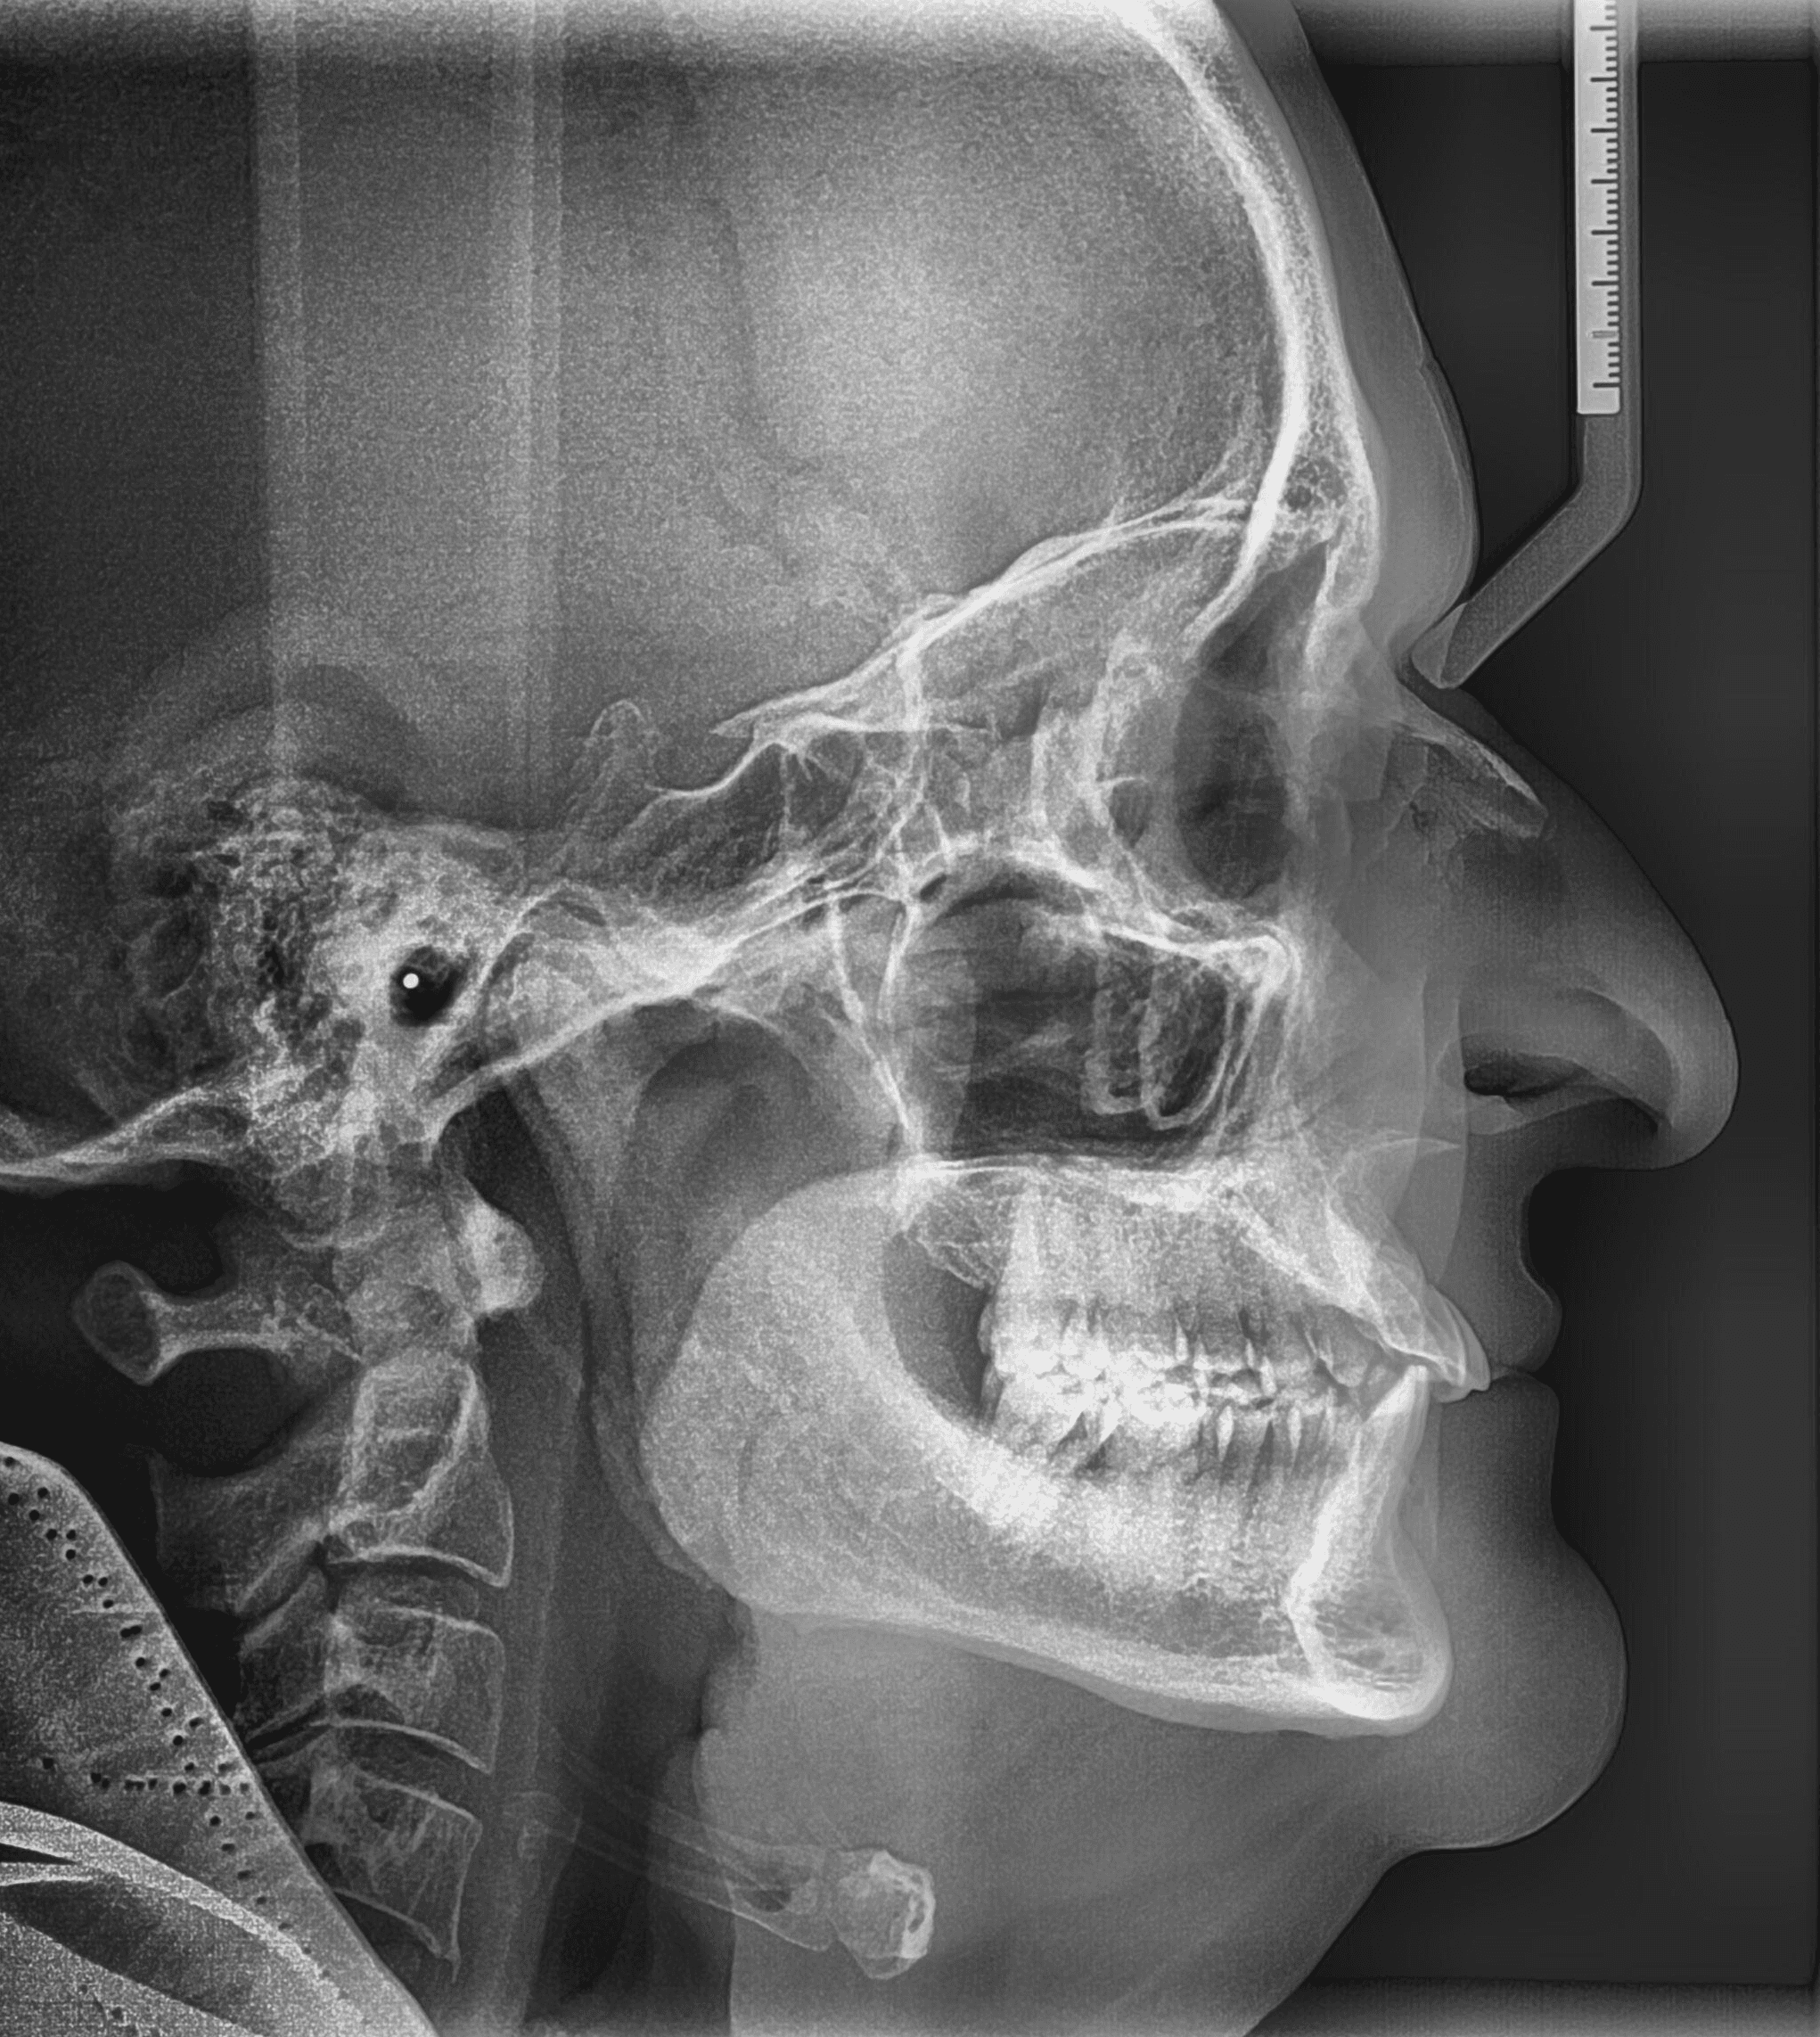

X-RAYS